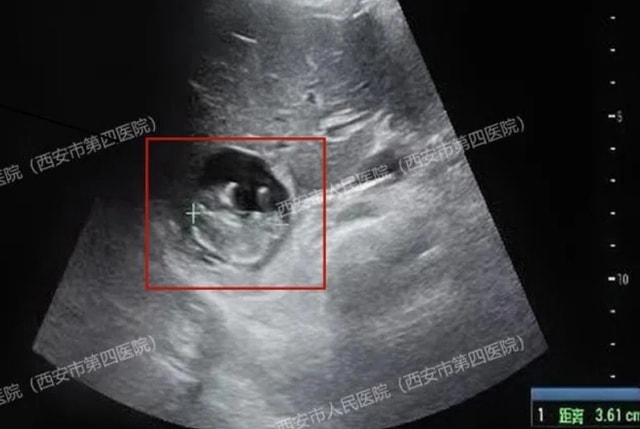

Trong lúc siêu âm, các bác sĩ ngạc nhiên khi phát hiện túi thai nằm trên bề mặt gan của người phụ nữ, một tình trạng cực kỳ hiếm gặp được gọi là "thai gan".

Một phụ nữ 40 tuổi họ Vương ở Tây An, tỉnh Thiểm Tây, Trung Quốc, gần đây đã đến bệnh viện để kiểm tra sau khi bị mất kinh 50 ngày. Xét nghiệm máu xác nhận cô đã mang thai. Tuy nhiên, kết quả siêu âm sau đó cho thấy không có túi thai trong tử cung hay ống dẫn trứng. Đội ngũ y tế tiếp tục điều tra và ngạc nhiên khi phát hiện túi thai nằm trên bề mặt gan của người phụ nữ, một tình trạng cực kỳ hiếm gặp được gọi là "thai gan", một loại thai ngoài tử cung nguy cơ cao và hiếm gặp.